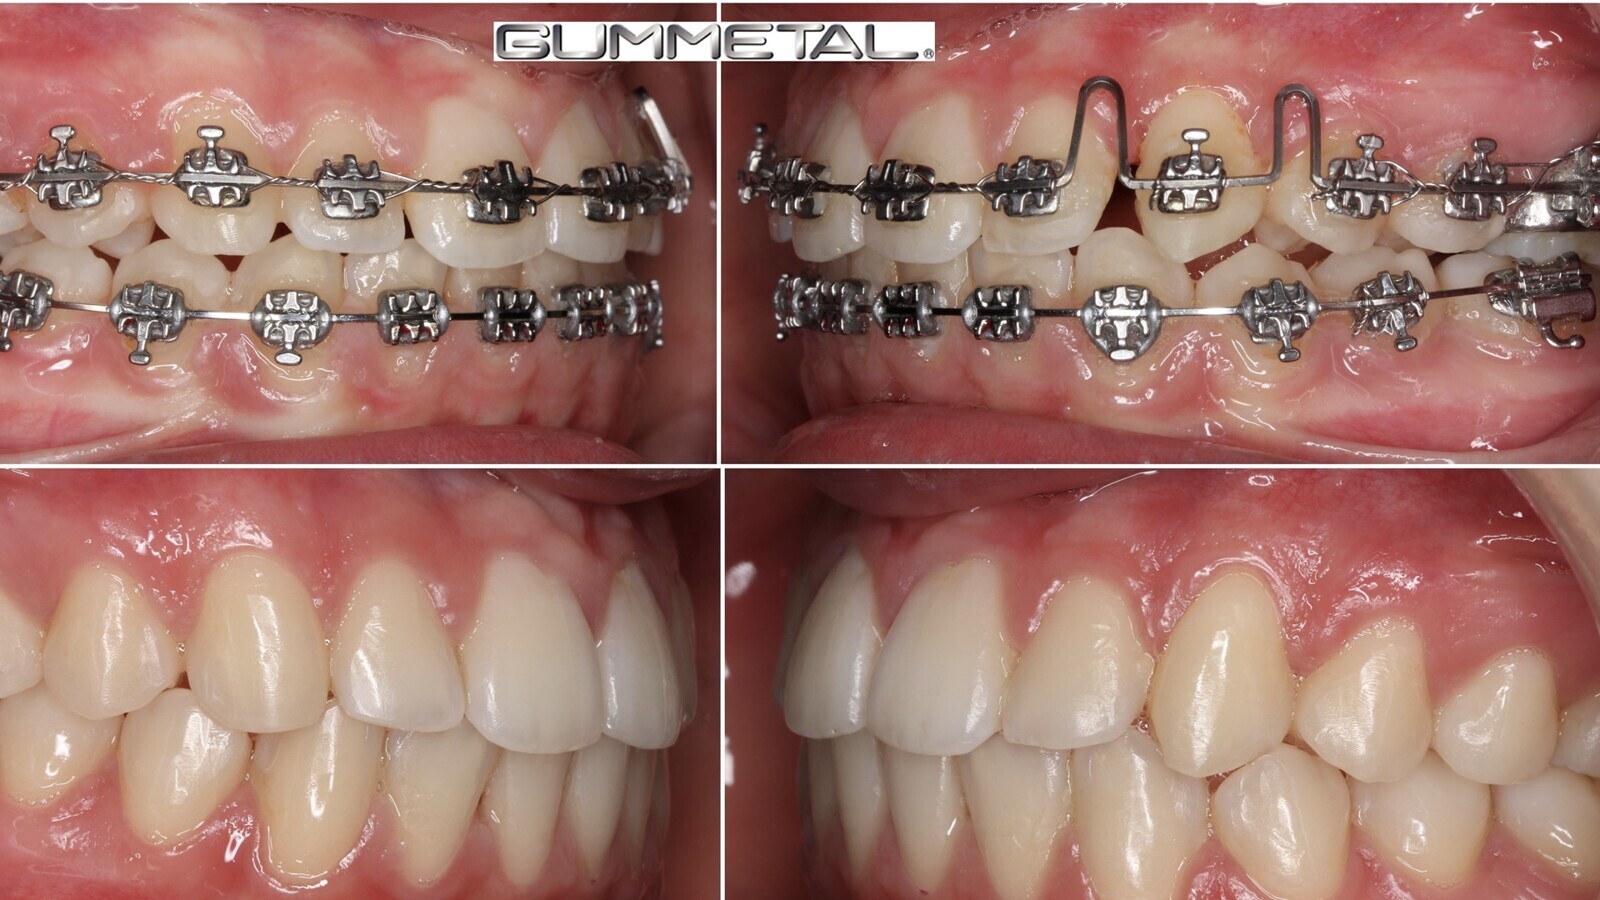

8. Una vez que se ha conseguido colocar en arcada la corona del canino, hay que realizar el trabajo hercúleo de dar torsión negativa a su raíz. Para ello recomendamos el uso de resortes en aleaciones de TMA o Gummetal con arcos gruesos (mínimo de 0.019x25”) y hacer entender al paciente la necesidad de tiempo para que el movimiento de torsión radicular negativa se produzca (figuras 17 y 18).

Figuras 17 y 18. Una vez colocada en arcada la corona del canino, hay que dar torsión negativa a su raíz. Se recomienda usar resortes en aleaciones de TMA o Gummetal con arcos gruesos.